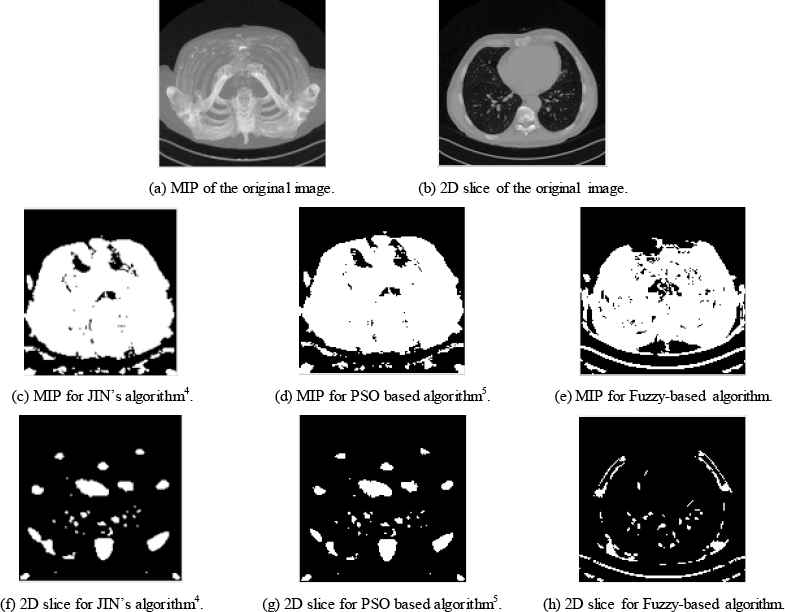

Figure 5 and table 3 give a similar comparison while using experimental CTA clinical data. The dataset used is VESSEL12. Obtained results assure that the proposed fuzzy based algorithm maintains the structure and the shape of the blood vessels where compared to the manual method and other automatic algorithm.

Case Study 3 CTA clinical data applied to three different algorithms.